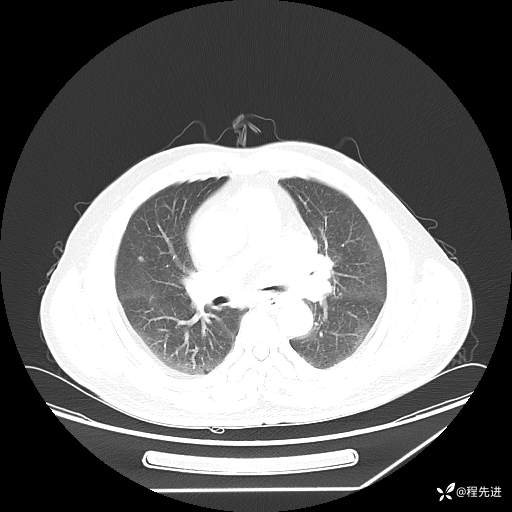

患者性别:男

患者年龄:57岁

简要病史:声嘶2月余

CT平扫+增强: